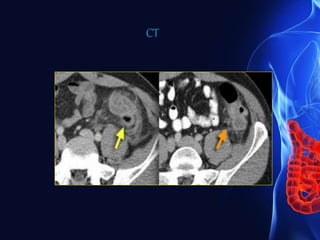

CT findings in acute appendicitis

90% diagnostic accuracy to detect acute appendicitis

• An appendix measuring greater than 6 mm in diameter

• Failure of the appendix to fill with oral contrast or air up to

its tip

• An appendicolith

• Enhancement of its wall with intravenous contrast

• Surrounding inflammatory changes include increased fat

attenuation, fluid, inflammatory phlegmon, caecal

thickening, abscess, extraluminal gas and

lymphadenopathy